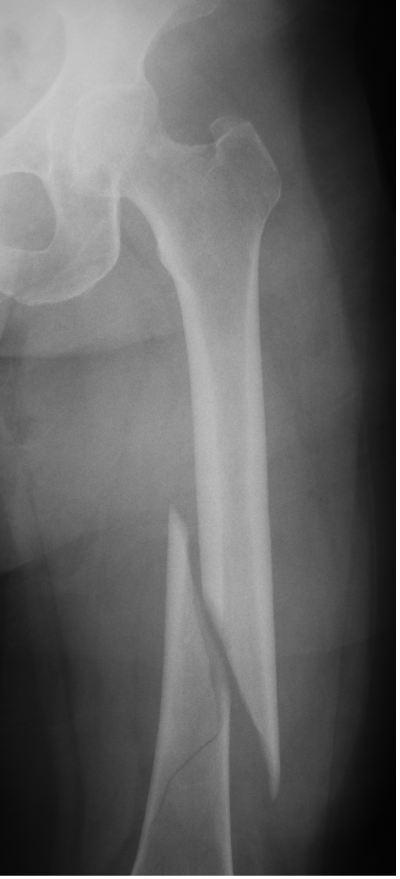

Femur fracture

age 13

Metatarsal fracture

age 16

Tibial fracture

age 57